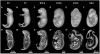

In this work, we report the use of iodine-contrast microCT to perform high-throughput 3D morphological analysis of mouse embryos and neonates between embryonic day 8.5 to postnatal day 3, with high spatial resolution up to 3µm/voxel. We show that mouse embryos at early stages can be imaged either within extra embryonic tissues such as the yolk sac or the decidua without physically disturbing the embryos. This method enables a full, undisturbed analysis of embryo turning, allantois development, vitelline vessels remodeling, yolk sac and early placenta development, which provides increased insights into early embryonic lethality in mutant lines. Moreover, these methods are inexpensive, simple to learn and do not require substantial processing time, making them ideal for high throughput analysis of mouse mutants with embryonic and early postnatal lethality.